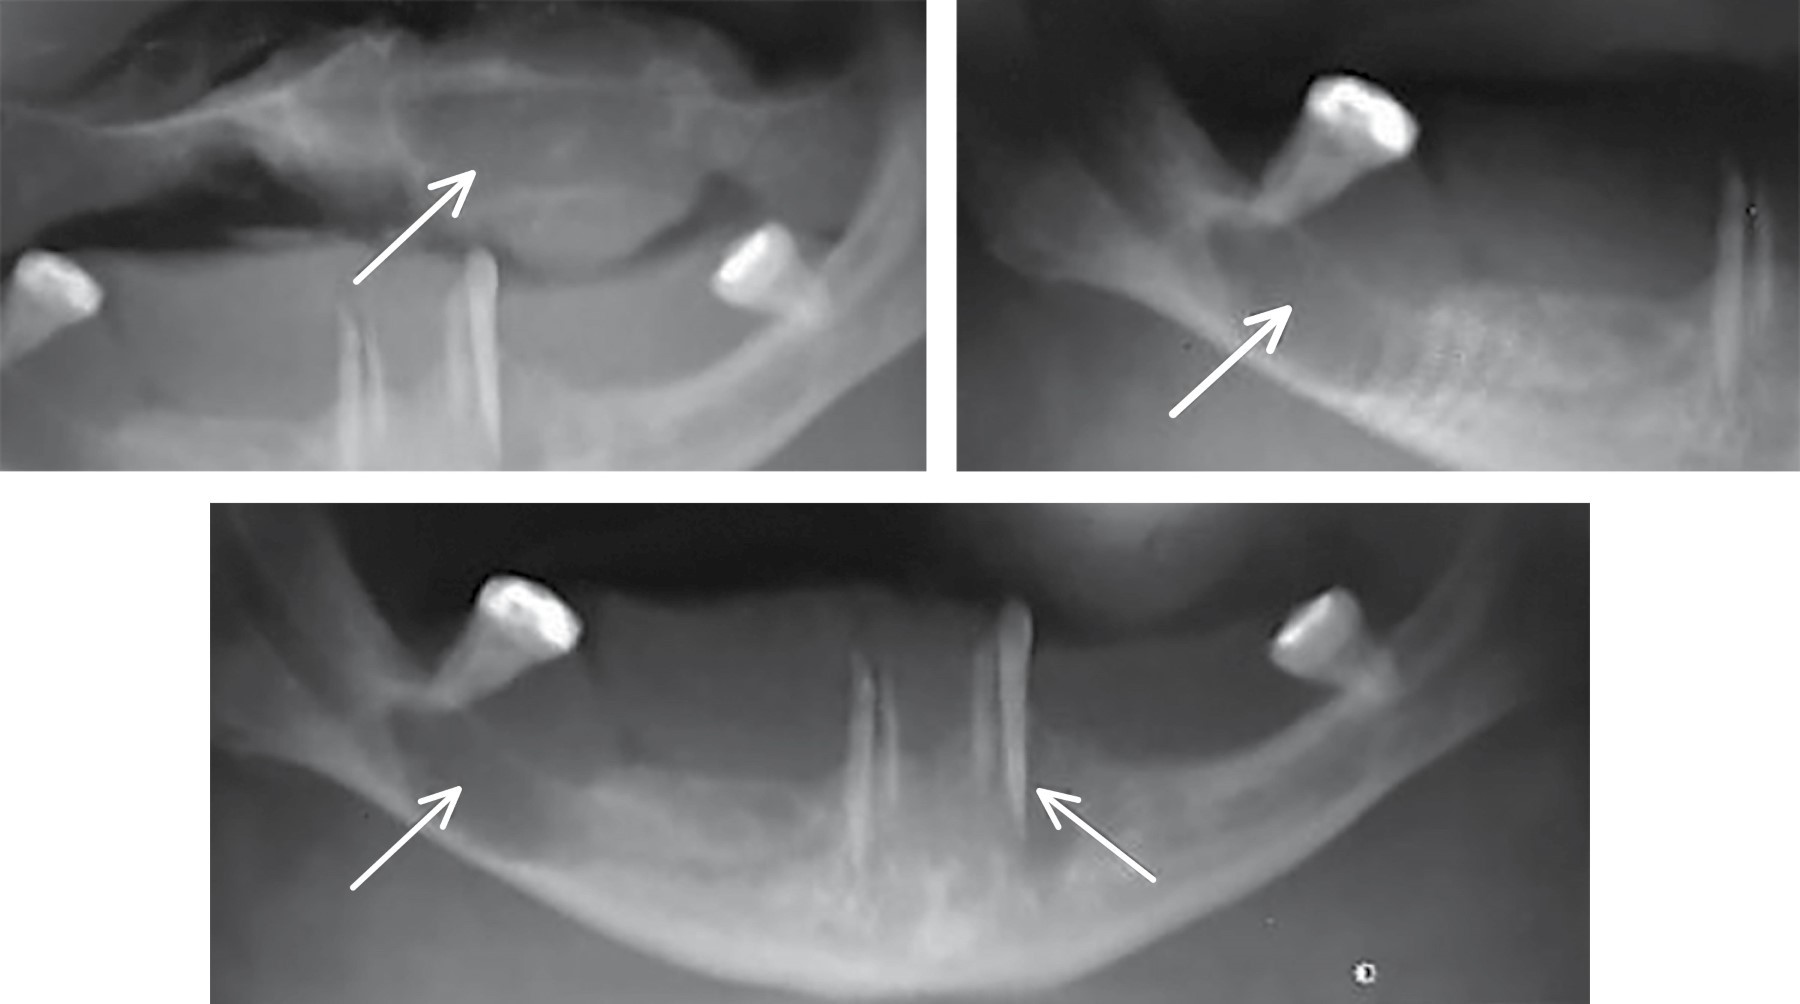

The following orthopantomogram is shown, which reveals radiolucent areas in the upper left maxilla and mandibular body (Figure 1).

Below is the radiograph of the patient showing the lytic lesions of the brown tumor due to tertiary hyperparathyroidism from Chronic Kidney Disease, which was managed by endocrinology (Figure 2A-B).

Once under treatment for HPT, the patient presented with an updated panoramic radiograph (Figure 2C), confirming partial involution of the lesions with an increase in bone density.